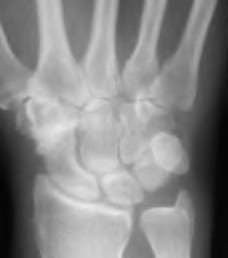

A 35-year-old woman reports wrist pain after a fall onto an outstretched hand. On exam, she has focal tenderness over the wrist snuffbox. A radiograph and CT image are shown in Figures A and B. What is the proper treatment of her injury?

Contrast enhanced MRA of the wrist is typically used to diagnose hypothenar hammer syndrome or other vascular abnormalities.